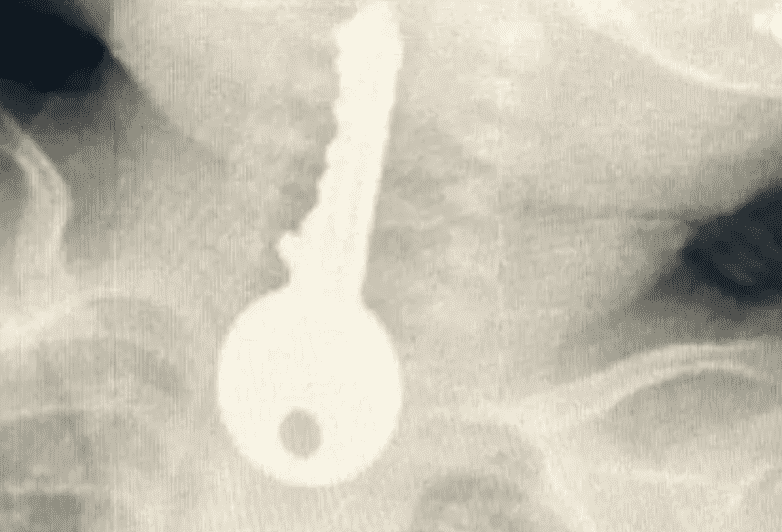

وكشفت الفحوصات وجود جسم غريب على شكل مفتاح في المريء.

كما أوضح الفريق المعالج للحالة أنه تم على الفور عمل منظار عاجل واستخراج مفتاح حديدي من المريء كاد أن يودي بحياته.